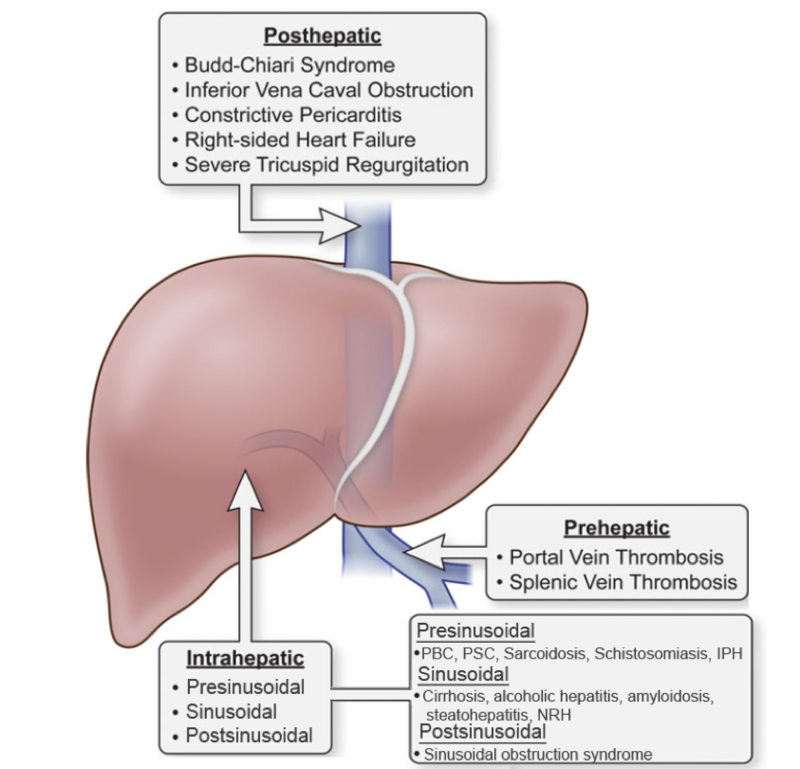

Portal Hypertension USMLE Step 1 Etiology Clinical Features

PORTAL HYPERTENSION CAUSES COMPLICATIONS DIAGNOSIS TREATMENT

Portal Hypertension Ppt Download